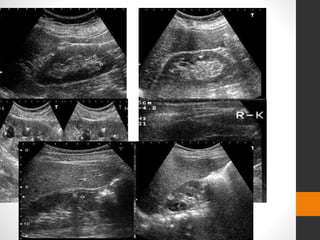

โ€ข Ultrasound usually demonstrates mild hydronephrosis

sensitivity (95%) but at the cost of a low specificity of

around 67%

โ€ข Highly echogenic foci with dense distal acoustic

shadowing

โ€ข Vesicoureteric junction

โ€ข relies on indirect visualization clues to identify stones

โ€ข less accurate than IVP or CT in diagnosis of ureteral

stones

โ€ข does not help in the evaluation of kidney function.

โ€ข 35% of patients acute ureteral obstruction do not

demonstrate any significant hydroureteronephrosis

โ€ข not reliable for small stones smaller than 5 mm

โ€ข dependent on operator skill